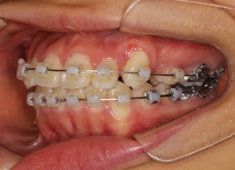

治療開始から11ヶ月後